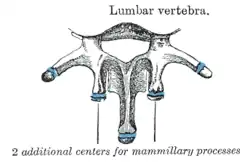

Three portions or tubercles can be noticed in a transverse process of a lower lumbar vertebrae: the lateral or costiform process, the mammillary process, and the accessory process.[2] The costiform is lateral, the mammillary is superior (cranial), and the accessory is inferior (caudal). The mammillary is connected in the lumbar region with the back part of the superior articular process. The accessory process is situated at the back part of the base of the transverse process. The tallest and thickest costiform process is usually that of L5.[2]

A lumbar vertebra seen from the side Ossification of lumbar vertebrae

Ossification of lumbar vertebrae